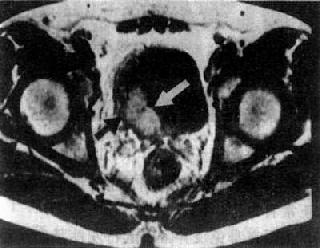

膀胱癌

图4-4-10 膀胱癌

膀胱腔内突起的肿块(白↓),

肿瘤已侵犯至壁外(黑↑)

MRI检查,尤其是增强扫描较有利于早期诊断和鉴别诊断以及肿瘤的分期(图4-4-10)。